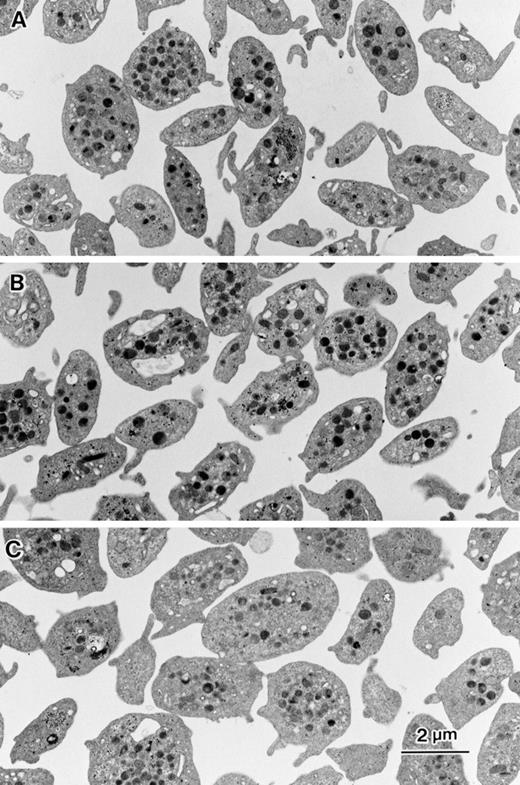

Ultrastructural analysis was performed to evaluate the effects of inhibitors on platelet shape, aggregation, and granule release. Unstimulated platelets showed discoid shape with small and short pseudopodia (Fig 7A). In the presence of 10 μmol/L DCB the platelets maintained discoid shape similar to control platelets (Fig 7B). However, platelets incubated with 80 μmol/L bepridil tended to be round shaped (Fig 7C). Fifteen-minute incubation of thrombin-stimulated platelets in the presence of 0.1% DMSO resulted in the formation of small aggregates (10 to 20 platelets). Each platelet showed pseudopodia formation and granule secretion (Fig 8A). In the presence of 10 μmol/L DCB, both pseudopodia formation and granule secretion were induced by thrombin, whereas the formation of platelet aggregates were markedly reduced (Fig 8B). Bepridil, similar to DCB, strongly inhibited aggregate formation by thrombin (Fig 8C). Although the pseudopodia formation was impaired, the stimulated platelets had no granules in the cytoplasm, suggesting that the release reaction had occurred even in the presence of bepridil (Fig 8C). These ultrastructural analyses confirmed the inhibitory effects of NCX inhibitors on platelet aggregation and also showed that granule secretion induced by thrombin occurred in the presence of NCX inhibitors. Thus, NCX inhibitors, particularly DCB, seemed to make platelets thrombasthenic.

Effects of DCB or bepridil on morphological changes evoked by thrombin. Washed platelets shown in Fig 7 were stimulated by 0.1 U/mL thrombin under unstirring condition. After 15 minutes of incubation, equal volume of 4% glutaraldehyde containing phosphate buffer was added to each aliquot. Electron microscopic analysis was performed as described in Materials and Methods.